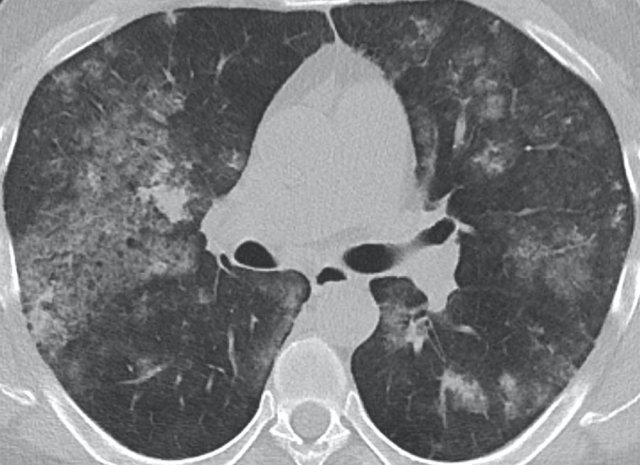

The image shows typical bilateral groundglass opacities in hypersensitivity pneumonitis with head cheese sign: a mixture of ground glass, normal density parenchyma and air trapping (circle).

NSIP